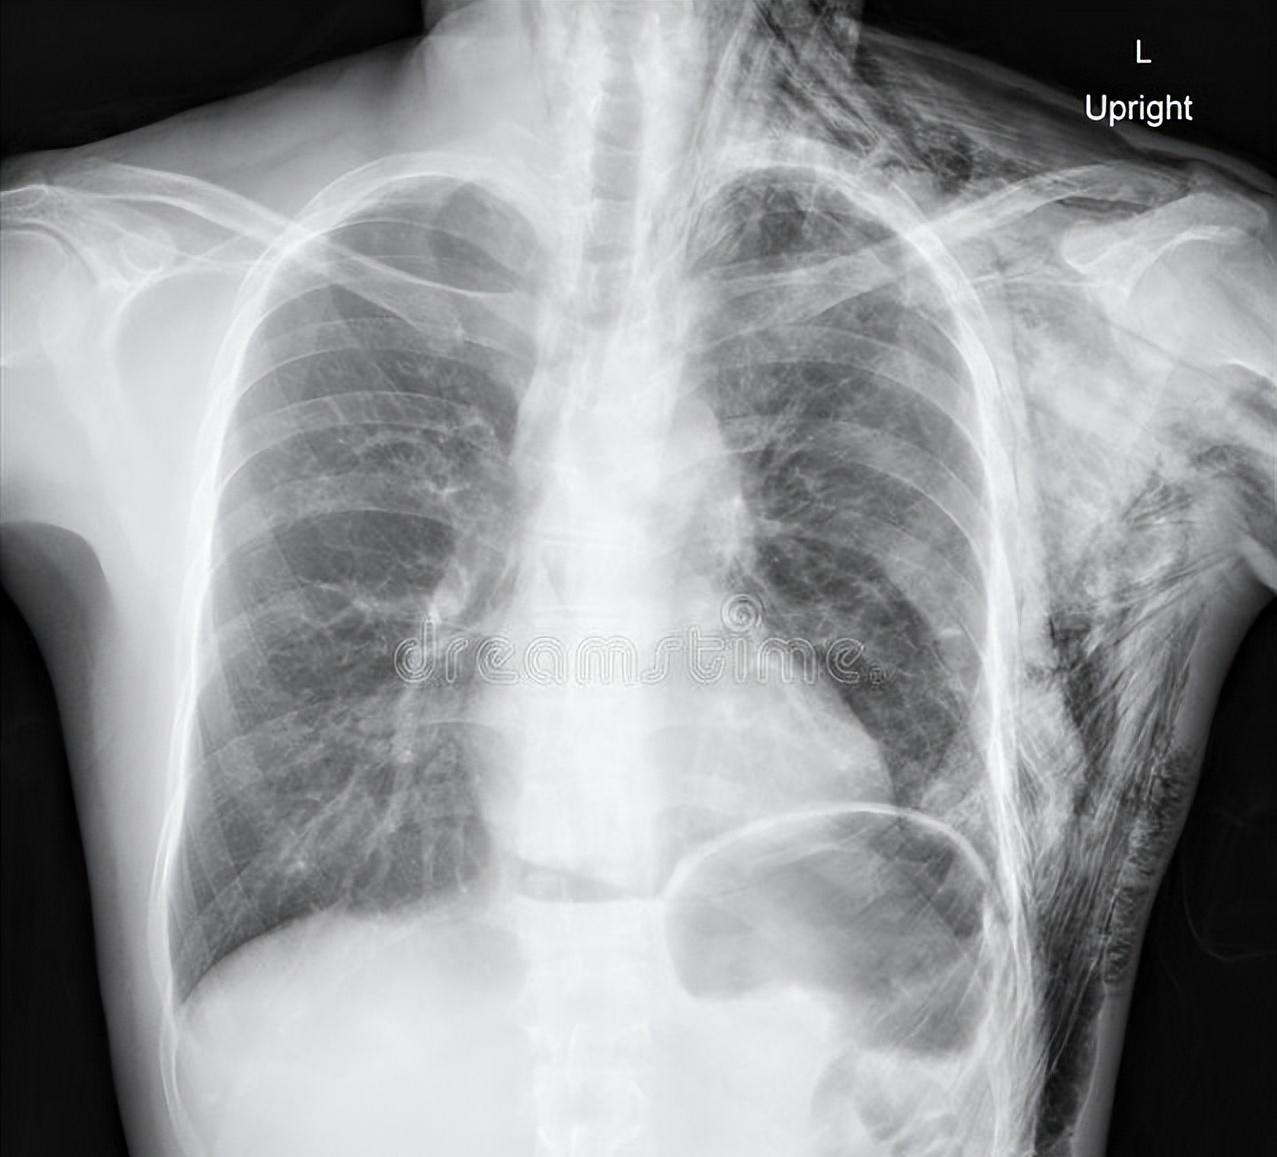

肺结节术后反复咳嗽?这些原因要分清 肺结节术后咳嗽是临床常见现象,多数患者会在术后1-3个月内出现,部分可持续更久。不少患者因此焦虑,担心病情复发。作为呼吸科医生,今天为大家梳理术后咳嗽的常见原因,帮大家科学应对。 最常见的原因是手术创伤刺激。肺部手术需切开气道、分离组织,会损伤支气管黏膜及周围神经,导致黏膜充血水肿、神经敏感性升高。即使手术顺利,受损组织修复过程中也会引发刺激性咳嗽,多为干咳或少量白痰,随黏膜愈合会逐渐缓解。 其次是气道高反应性。手术创伤会改变气道结构,使气道对冷空气、烟雾、粉尘等刺激异常敏感,形成类似“过敏性咳嗽”的表现。尤其术前有哮喘、慢性支气管炎病史的患者,术后气道高反应更明显,咳嗽可能更剧烈且持续时间更长。 术后感染或炎症残留也会诱发咳嗽。若术后出现咳痰增多、痰色发黄、发热等症状,可能是气道或肺部发生感染,需及时复查血常规、胸片,针对性使用抗感染药物。此外,术后胸腔内少量积液、积气,也可能刺激胸膜引发咳嗽。 少数情况下,咳嗽可能与肺功能异常相关。手术切除部分肺组织后,肺通气、换气功能暂时受影响,身体通过咳嗽排出分泌物,适应新的肺功能状态。若咳嗽持续超过3个月,或伴随咯血、胸痛加重,需警惕支气管胸膜瘘、肿瘤复发等特殊情况,及时就医排查。 术后咳嗽多数为正常恢复过程,可通过多喝水、避免刺激、遵医嘱使用止咳药缓解。但需牢记“异常情况早排查”,出现上述警示症状及时复诊,才能安心康复。关注肺结节肺结节[超话]